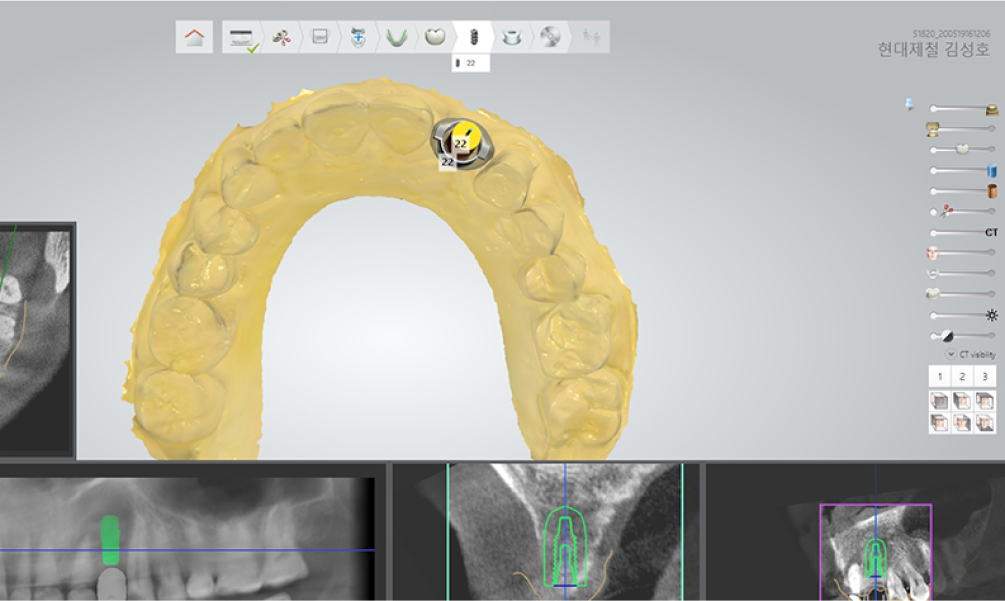

STEP 01 디지털 진단 & 컴퓨터 시뮬레이션

3D-CT를 이용해 치아를 정밀하게 분석하여 치아의 상태를 확인하며, 이 자료를 바탕으로 컴퓨터 시뮬레이션을 진행하여 임플란트 식립에 대한 모의수술을 통해 치료 계획을 세웁니다.